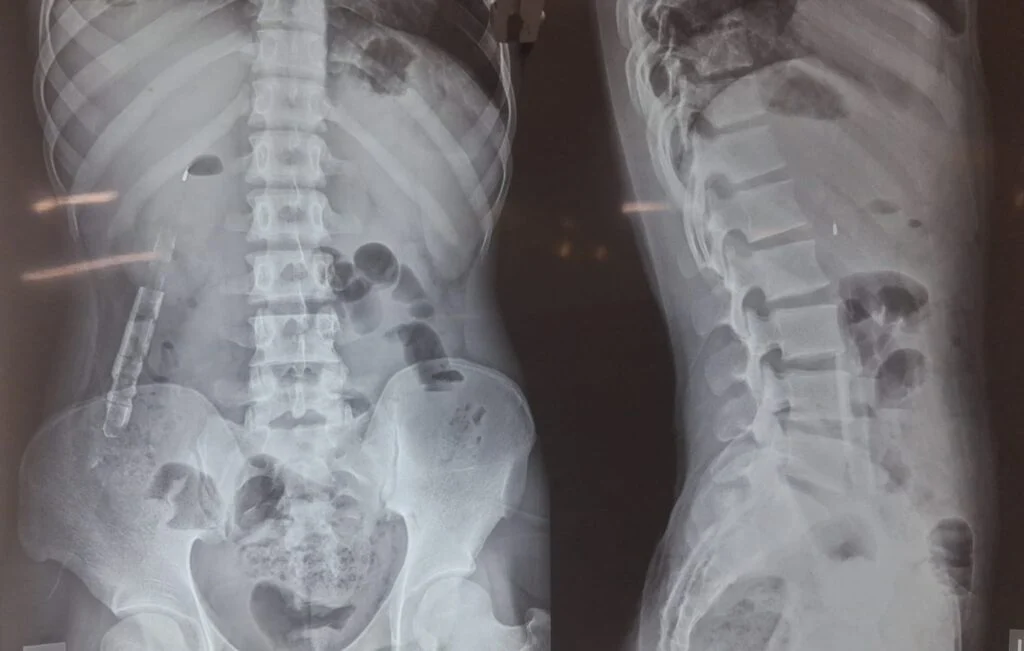

যুবকের পরিবার সূত্রে জানা যায়, মালদার রঘুনাথগঞ্জের বরজুমলা কলোনীর বাসিন্দা রহমত প্রায় পাঁচ বছর থেকে পেটে ব্যথায় ভুগছিল। স্থানীয় চিকিৎসাকেন্দ্র থেকে চিকিৎসা করেও ব্যথা কমেনি। এমনকি এক্স-রে করার পরেও তা ফলপ্রসূ হয়নি। এরপর কলকাতার Repose Clinic & Research Centre এ আসে। তারপর সেখানকার চিকিৎসকদের পরামর্শ অনুযায়ী ওই যুবকের কোলোনোস্কোপি করা হয়।

আর সেই পরীক্ষার পরই জানতে পারা যায় যে, রহমতের পেটের মধ্যে একটি পেন আটকে রয়েছে। এরপরই ডক্টর ইন্দ্রনীল সাহা, ডক্টর সৈকত দাস ও ডক্টর সমরেন্দ্র নাথ বসাকের তৎপরতায় প্রায় দেড় ঘন্টা ধরে চলা এই জটিল অপারেশন সফলতা পেল। আর আটকে থাকা গোটা কলমটিও অক্ষত অবস্থায় উদ্ধার করা হলো। রহমতের এই সুস্থতার কারণে দুশ্চিন্তায় হতাশ হয়ে পড়া পরিবারের মুখে হাসিও ফিরে এসেছে। আর রহমতও নিজের নতুন জীবন ফিরে পেল।